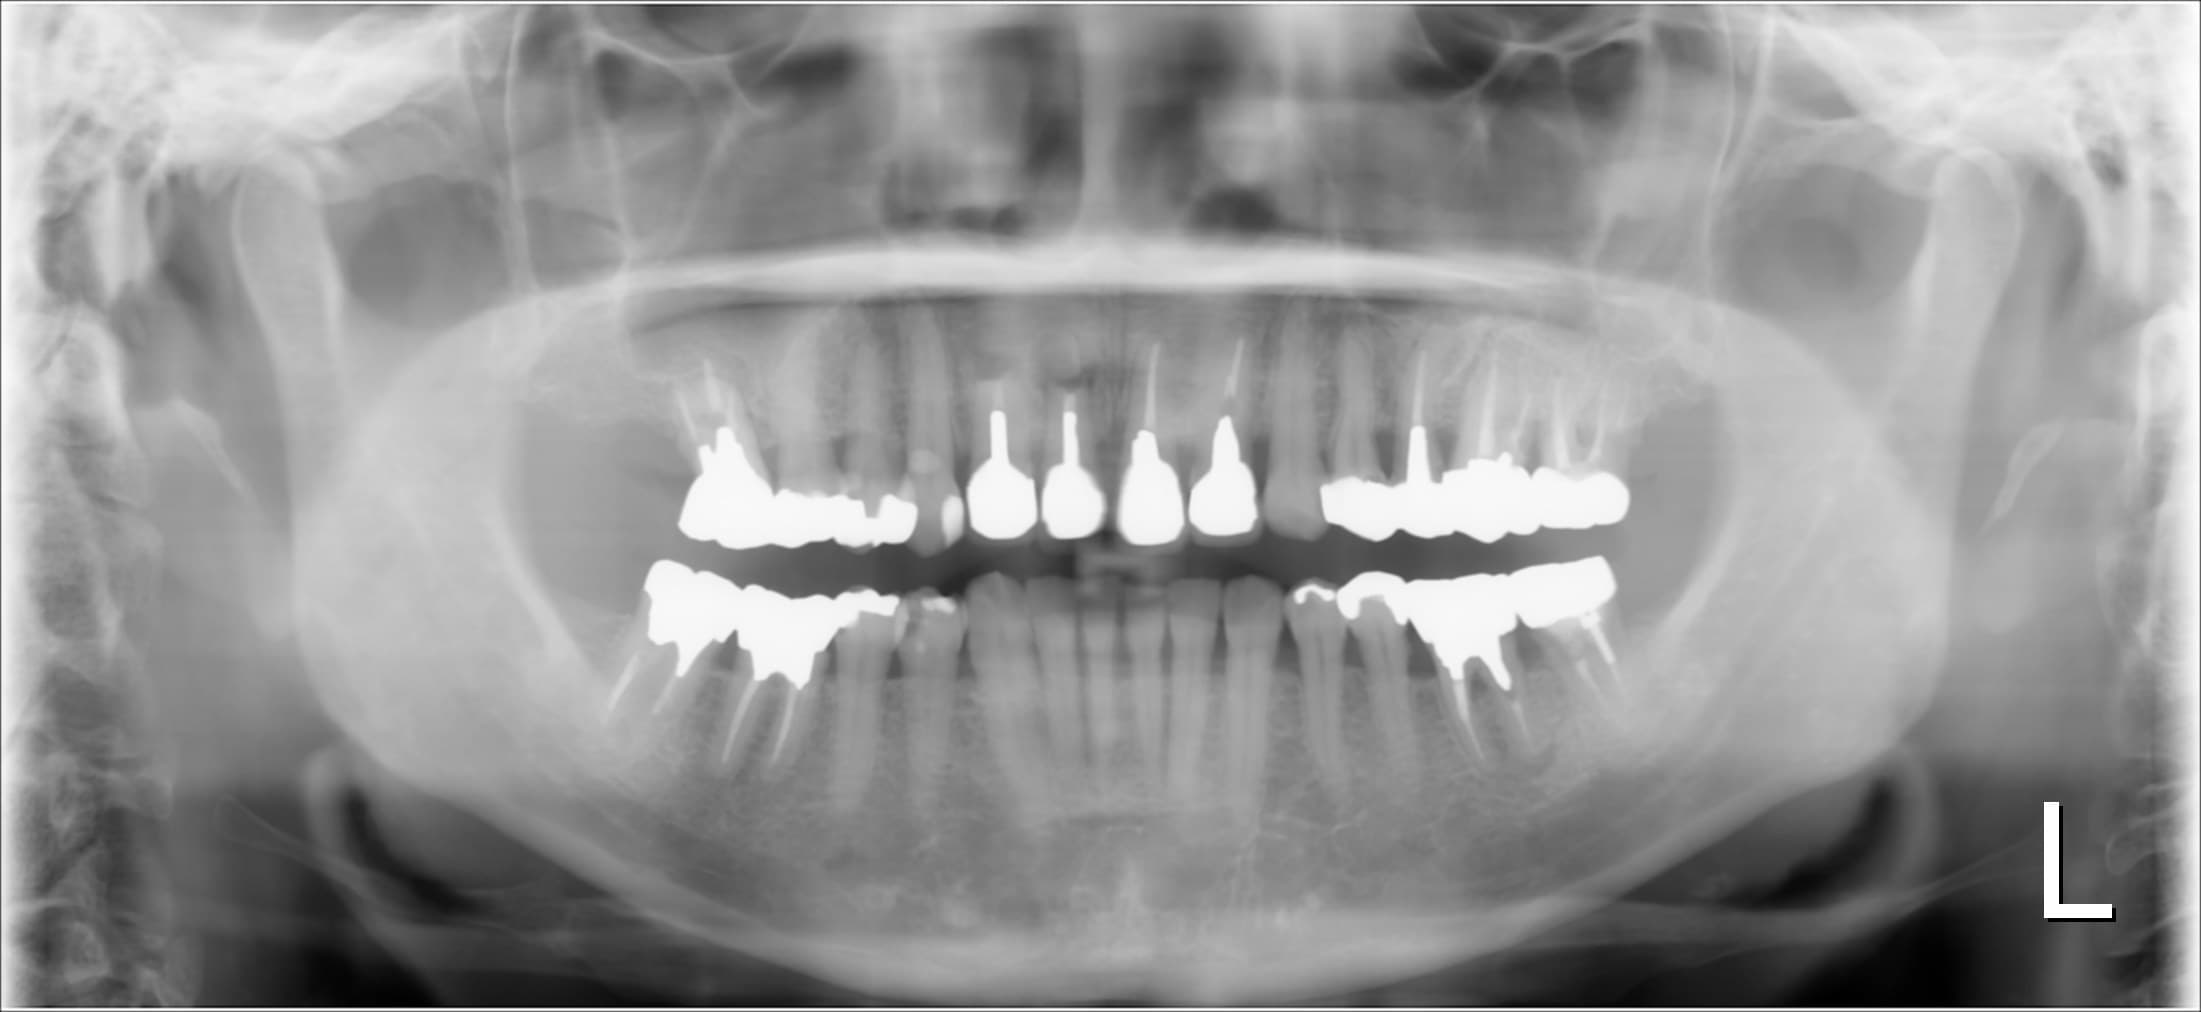

今回ご紹介する歯周専門治療のケースは、50代女性の方です。

初診時の状況は、歯周病の進行も非常に深刻で、一部では歯を支える骨が大きく溶けて排膿や出血は勿論、歯の動揺も認められる状態でした。

(上記の写真は1回目の仮歯を入れて撮影したものです。)